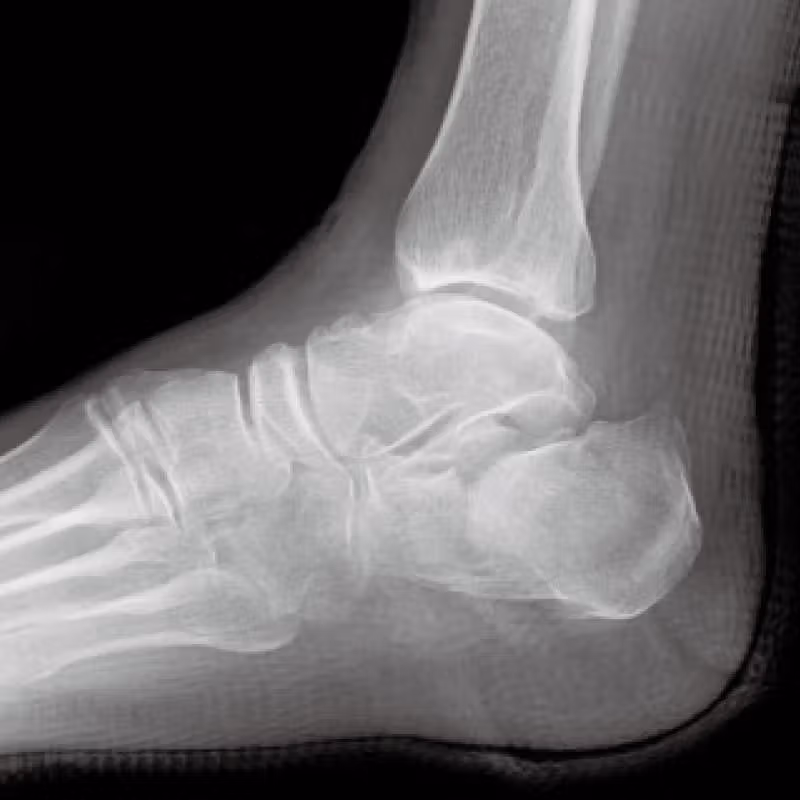

[踵骨骨折 骨接合術]